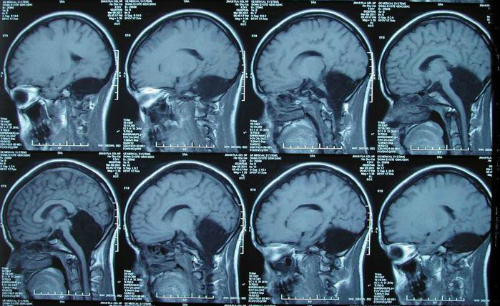

Đầu năm 2014, một người phụ nữ 24 tuổi sinh sống tại Sơn Đông, Trung Quốc đã phát hiện mình không hề có phần tiểu não - nơi chiếm đến 50% các tế bào thần kinh nhưng cô vẫn sống tốt, lấy chồng và sinh con như những người bình thường khác, tuy nhiên, người phụ nữ này chỉ bị ảnh hưởng vận động nhẹ, phát âm hơi lắp bắp.

Ảnh chụp X-Quang chứng vô tiểu não nguyên phát

Theo các nhà nghiên cứu, đây là điều vô cùng độc đáo và là tiền đề cho các nghiên cứu sau này, đây cũng là một minh chứng cho sự linh hoạt, sức mạnh kỳ diệu của bộ não.